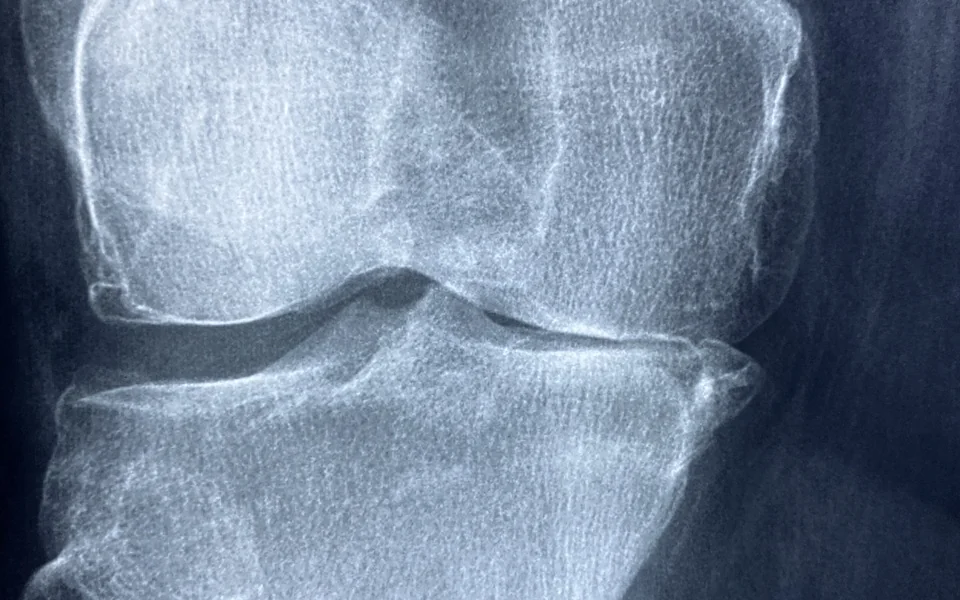

연구에 따르면, 노화가 진행됨에 따라 체내 염증 수치는 상승하는 경향이 있습니다. 노화에 따른 면역 체계의 약화는 염증 반응을 더욱 길고 강하게 지속시킬 수 있습니다. 이러한 만성 염증은 심혈관 질환, 당뇨병, 관절염과 같은 다양한 질환의 원인이 될 수 있으며, 이는 개인의 삶의 질을 떨어뜨리는 요인이 됩니다. 따라서 노화 과정에서 염증을 관리하는 것은 매우 중요합니다.